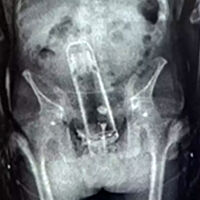

При стандартном рентгеновском осмотре сотрудники учреждения обнаружили в теле мужчины металлический предмет, который оказался термосом. По словам шерифа округа Полк Грейди Джаджа, «задержанный принес термос в тюрьму самым необычным способом».